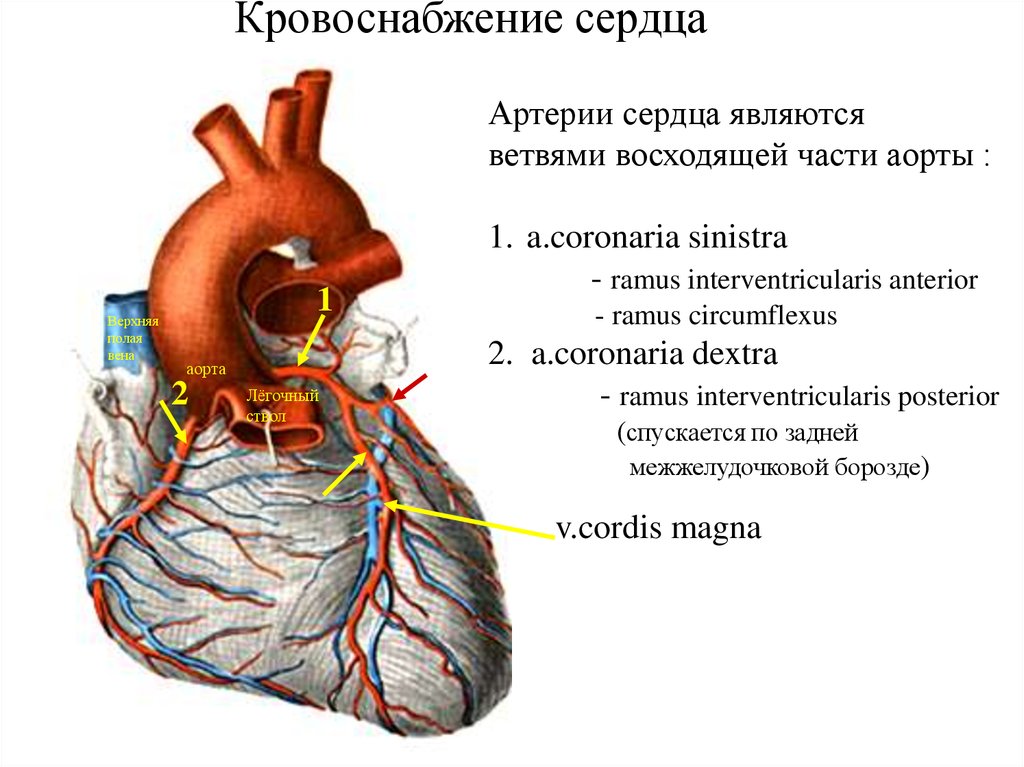

Анатомия коронарных артерий: КТ-изображения